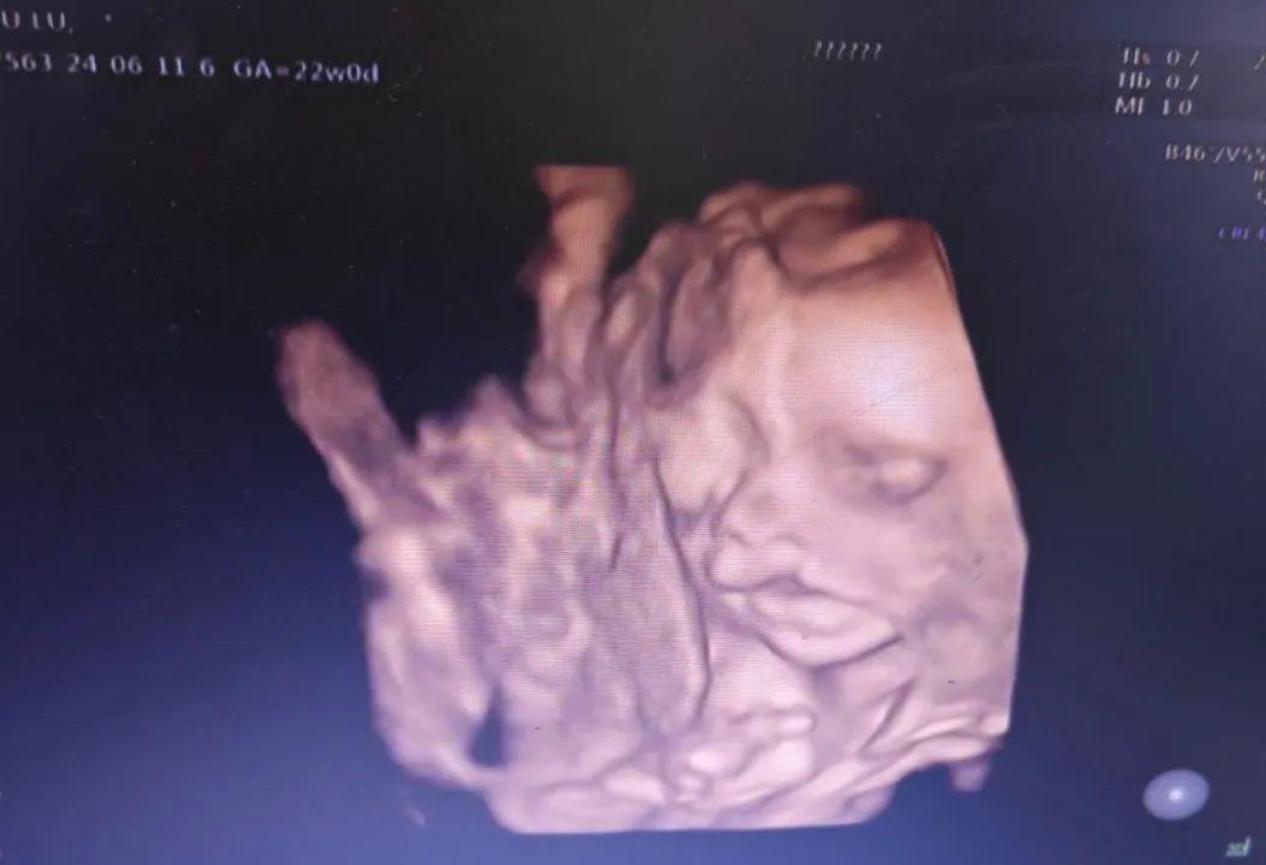

小燕跟老公結婚之後,備孕了好幾年才懷上了孩子,兩夫妻都非常的開心,小燕在22周進行排查的時候,特地選擇了一個可以讓老公進去看孩子的醫院進行四維彩超檢查。

檢查開始,老公就目不轉睛地盯着B超機裏面孩子的樣子,看到孩子的頭大大的,四肢還非常的活躍,沒一會兒看到孩子的臉轉過來了,爸爸瞬間就知道這個就是我的孩子,因爲孩子的樣子和神態有點像爸爸,最重要的是這個孩子在B超機裏面總是咧開嘴大笑,看起來笑得特別開心,特別的可愛

B超醫生卻一直盯着B超機裏面的胎兒看,一邊看一邊皺眉,特別是在孩子的嘴巴那一塊就看得更加仔細,然後皺着眉跟小燕和老公說:這個孩子看這樣子是有問題的,你看他的嘴巴,笑的時候臉的很開,這個就是兔脣

而且他這個兔脣看起來比較嚴重,出生之後需要修復的會比較多,而且剛出生的時候奶也喝不到,這會影響孩子的營養的攝入,所以建議還是流產,再要下一個孩子吧。